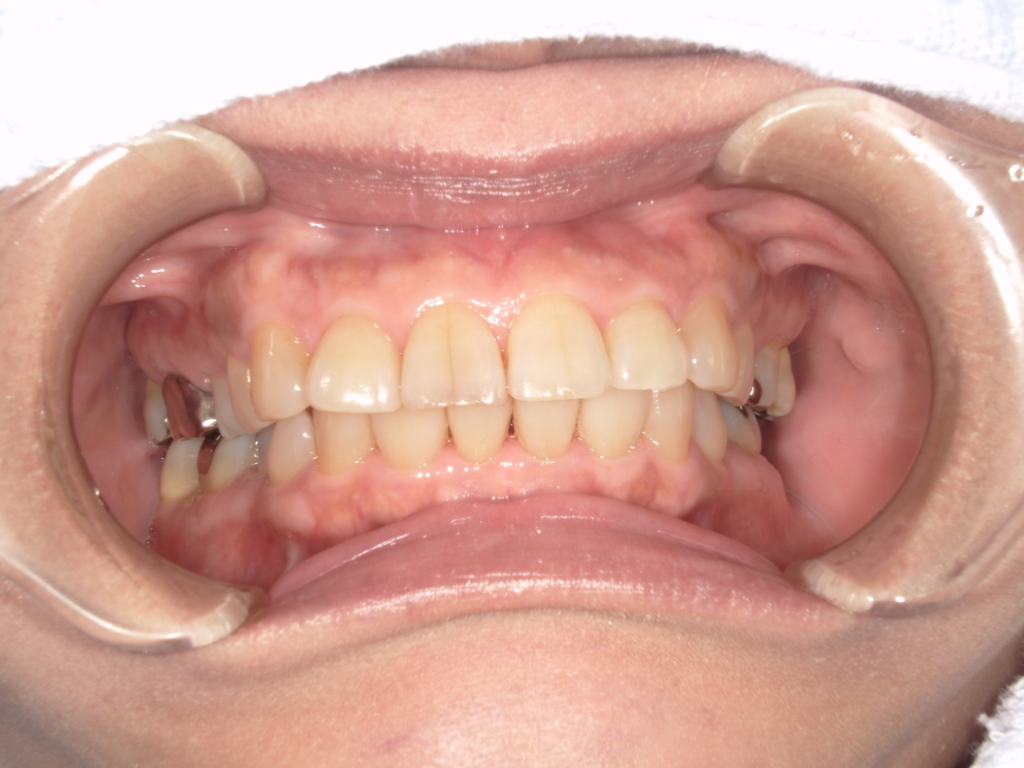

Y様インプラント実例 #44

左の上下の奥歯をインプラントで治療しています。

左下の奥歯は歯を抜くのと同時にインプラントの埋め込みを行っています。

被せものは上下、セラミックスで作っています。

治療前

治療後